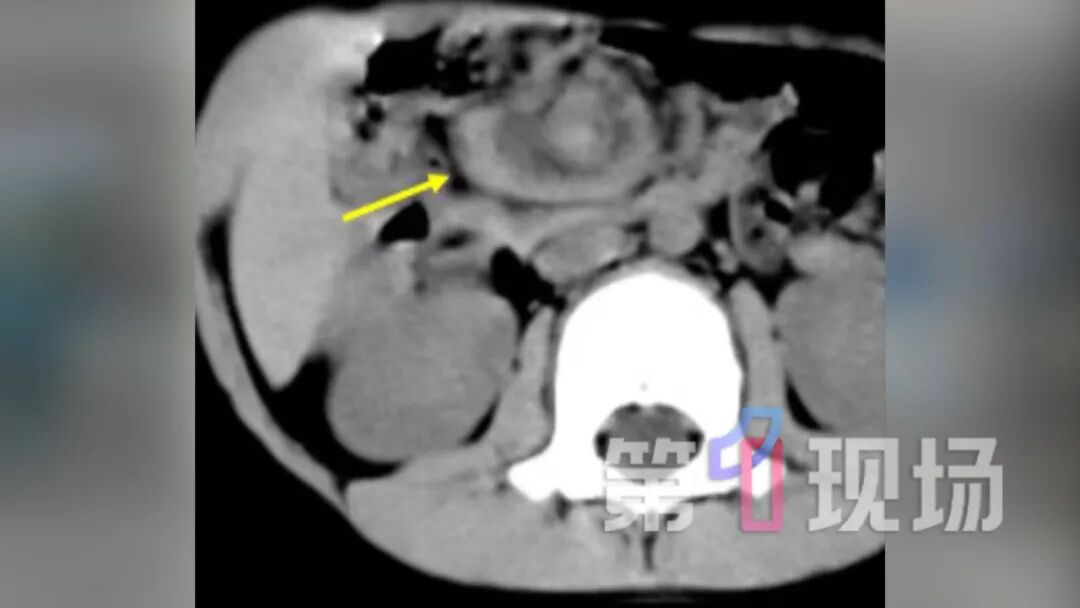

我们高度怀疑他是小肠扭转的情况。 CT做完后,当天晚上12点我们就把患者送到手术室做了腹腔镜的探查,证实了他是先天性肠旋转不良,伴有中肠扭转了720度,相当于肠子转了两圈。

医疗团队争分夺秒为乐乐实施了急诊腹腔镜微创手术。手术中发现,乐乐的肠管及供应血管拧了一个“大麻花”。万幸,家属送医相对及时,经过手术和精心的护理,乐乐的肠管得以保住,后续已顺利康复出院。